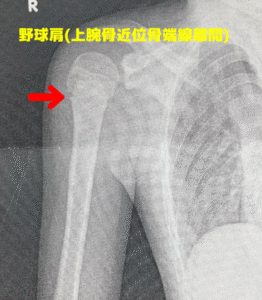

下記の写真が野球肩のレントゲン写真。

→矢印の部分が、骨端線離開を起こしています。